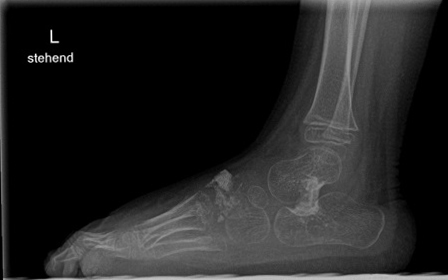

Röntgen Fuß AP und seitlich im Stand oder belastungssimuliert (Abb.1,2).

Röntgen seitlich in maximaler Plantarflexion bei Unklarheit über die Flexibilität.

Standaufnahme des oberen Sprunggelenkes: Bei Verdacht auf Instabilität oder Fehstellung des oberen Sprunggelenkes.